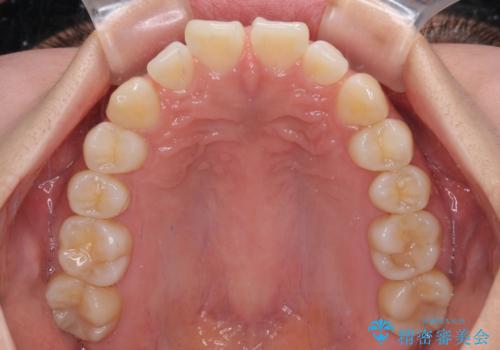

- 上顎前歯の隙間を気にして来院された患者様です。

下顎前歯が上顎前歯に食い込むような咬み合わせにより、上顎前歯が開いてしまっていたため、咬合高径の挙上により突き上げを改善するよう、インビザラインにより矯正治療を行うこととしました。

咬合高径の挙上により上顎前歯の突出感も改善することができ、整った口元となりました。